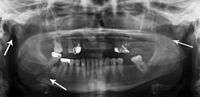

Panoramic radiographs are tomograms where the mandible is in the focal trough and show a flat image of the mandible. Because the curve of the mandible appears in a 2-dimensional image, fractures are easier to spot leading to an accuracy similar to CT except in the condyle region. In addition, broken, missing or malaligned teeth can often be appreciated on a panoramic image which is frequently lost in plain films. Medial/lateral displacement of the fracture segments and especially the condyle are difficult to gauge so the view is sometimes augmented with plain film radiography or computed tomography for more complex mandible fractures.

Research has shown that panoramic radiography is similar to computed tomography in its diagnostic accuracy for mandible fractures and both are more accurate than plain film radiograph.[11] The indications to use CT for mandible fracture vary by region, but it does not seem to add to diagnosis or treatment planning except for comminuted or avulsive type fractures,[12] although, there is better clinician agreement on the location and absence of fractures with CT compared to panoramic radiography.[13]

Panoramic radiograph of a simple mandible fracture of the right mandibular body, minimally displaced. Note that the teeth to the left of the fracture do not touch- lateral oblique image demonstrating a fractured mandible.